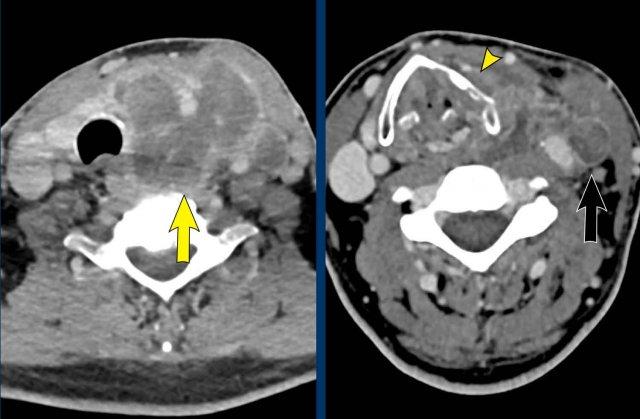

Bệnh nhân nam trẻ tuổi bị tai nạn khi tham gia đua xe mô tô địa hình.

Bệnh nhân được nhập vào khoa ICU với nhiều chấn thương.

Sau ba ngày, bệnh nhân hồi phục ý thức và được ghi nhận có liệt nửa người bên phải, không thể giải thích bằng bất kỳ tổn thương não nào.

Bệnh nhân cũng có hội chứng Horner bên phải.

Hình ảnh

CT lúc nhập viện cho thấy gãy mỏm ngang C7 và gãy xương sườn thứ nhất (đầu mũi tên).

Trên CECT có hiện tượng thoát thuốc cản quang cho thấy đang chảy máu tích cực (vòng tròn).

Continue with the MRI…

Đầu tiên, siêu âm vùng cổ được thực hiện để tìm kiếm tổn thương đứt rễ thần kinh, tuy nhiên việc khảo sát này bị hạn chế do các thay đổi chấn thương ở vùng này.

Sau đó, chụp MRI được thực hiện.

Hình ảnh cắt ngang cho thấy sự tăng cường tín hiệu của các rễ thần kinh, gợi ý tổn thương đám rối thần kinh cánh tay.

Cũng lưu ý tổn thương phần mềm cạnh cột sống bên phải.

Continue….

Ngoài ra, hình ảnh T2W cho thấy một số tín hiệu cao nhẹ trong tủy sống bên phải (mũi tên).

Điều này được xem là bệnh lý tủy sống sau chấn thương và cũng có thể là giải thích cho hội chứng Horner bên phải.